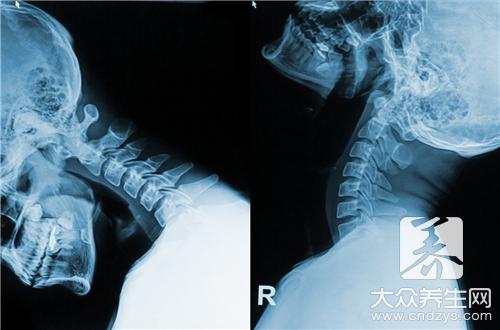

随着生活节奏的加快,坐在电脑前面辛苦奋斗的人越来越多,这个时候劲椎病患者也会越来越多。患了颈椎病没有时间按摩理疗可怎么办?心疼家人的朋友们可以通过食疗的方法为他们治疗颈椎病哦!那么颈椎病如何进行食疗呢?

颈椎病如何进行食疗